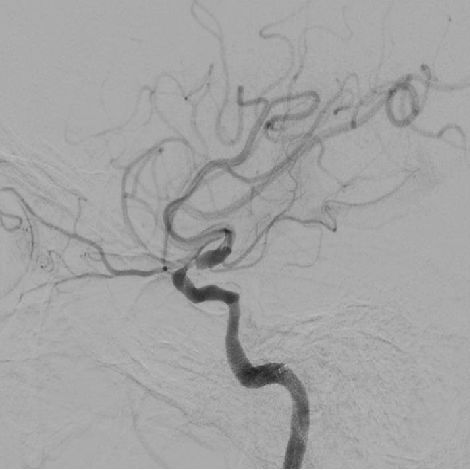

造影可见前交通动脉开放,双侧大脑中动脉显影,左侧颈内动脉末端显影;左侧颈内动脉颈段以远未见显影。

1、造影可见左侧颈总动脉和主动脉弓呈锐角,尝试泥鳅导丝+125cm多功能导管引导8F导引导管超选左侧颈总动脉时,导引导管无法送达,更换6F长鞘超选至左侧颈内动脉颈段,撤出导丝及多功能导管,考虑主动脉弓处张力较大,遂选择具有良好支撑性的React™ 68 远端通路导管替代中间导管。

React™ 68导管内造影见床突段显影浅单,以远未见显影

2、SWIM操作:0.014”微导丝+Rebar 18微导管通过LMCA M1段,手推造影剂示真腔,撤出微导丝,通过微导管将Solitaire 6-30支架输送至M1段,缓慢释放支架,远端在M1中段,近端在床突段,造影可见左侧前向血流部分恢复,眼动脉显影良好,眼动脉段可见充盈缺损。等待5分钟,推送React™ 68导管至支架近段,负压抽吸并缓慢回撤支架,然后撤出导管。可见支架体附着质软红色血栓,导管内抽出大量细碎的栓子。

3、造影可见左侧颈内动脉前向血流恢复,M1段以远显影良好,眼动脉段可见重度狭窄,观察5分钟后,再次造影,眼动脉段以远血流速度明显下降,局部造影剂滞留,考虑与对侧前交通动脉的代偿供血形成湍流,有再次形成血栓的可能,遂对狭窄部位进行球囊扩张。